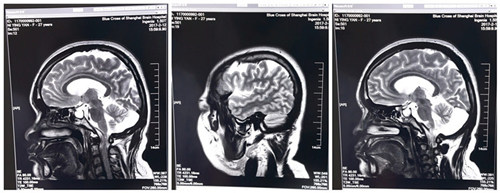

術(shù)前:雙側(cè)側(cè)腦室旁、半卵圓中心及額頂葉多發(fā)灶

術(shù)前各項(xiàng)準(zhǔn)備工作準(zhǔn)備周全后,3月2日,倪紅的手術(shù)順利進(jìn)行。手術(shù)全麻,以左側(cè)為主。術(shù)中見腦部發(fā)育不良,腦回肥大,皮層電極反復(fù)監(jiān)測,額葉中央前區(qū)、中央?yún)^(qū)、顳葉散及顳中回深部均見異常放電節(jié)律,仔細(xì)剝離粘連組織并分區(qū)切除病變組織,再次腦電檢測顯示暴露區(qū)無異常放電,術(shù)畢,功能區(qū)重要血管保護(hù)完好,患者安返ICU進(jìn)行術(shù)后監(jiān)護(hù)。